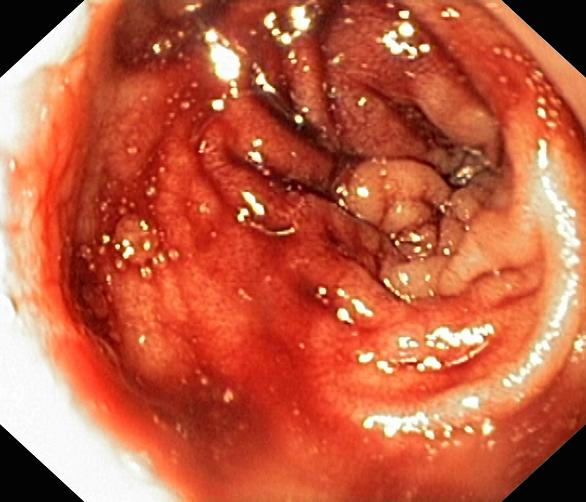

Krwawienie